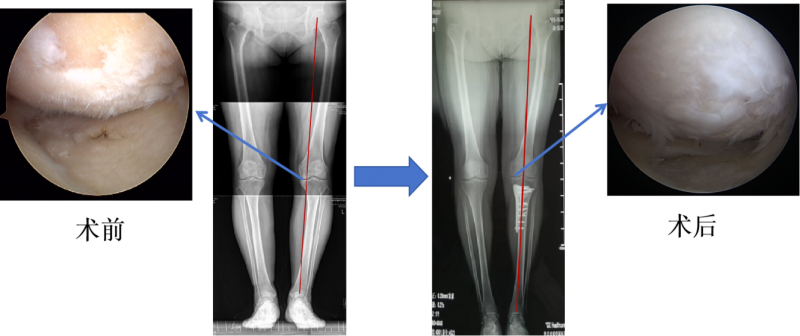

KOA往往会造成关节软骨的磨损,一直以来我们都认为,这种磨损是不可逆的,关节软骨是不可再生的。但是近几年我们观察发现,接受了胫骨高位截骨手术的患者,他们的膝关节内侧原先因为负重过大而磨损的软骨得到了不同程度的修复。虽然这些再生的软骨与受损前的软骨相比性状、功能有所欠缺,但这一现象仍然表明了保膝手术能够明显的减轻受损的膝关节内侧的压力,是有显著疗效的。

胫骨高位截骨术主要用于治疗以内侧间室退变为主的膝骨关节炎。通过针对胫骨的截骨矫形,纠正下肢力线,在内外侧关节间室重新分配应力负荷,从而起到治疗膝骨关节炎的效果。在矫正下肢力线后的患者中,异常应力负荷的去除改善了力学微环境,在改善患者症状的同时观察到了受损软骨的再生和炎症的缓解。